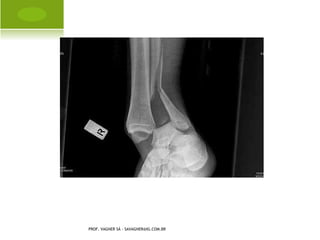

ESPORÃO

PROF. VAGNER SÁ - SAVAGNER@IG.COM.BR